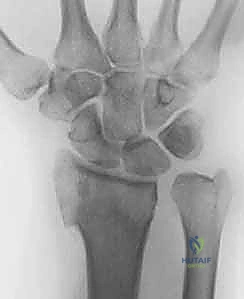

بروتوكول التصوير الطبي المتقدم

لا يكتفي الدكتور هطيف بالفحص السريري، بل يعتمد على أحدث تقنيات التصوير لضمان "الأمانة الطبية" في التشخيص:

1. الأشعة السينية (X-rays): بوضعيات متعددة (أمامية خلفية، وجانبية دقيقة). الوضعية الجانبية الحقيقية (True Lateral) حاسمة لاكتشاف أي خلع جزئي في المفصل (DRUJ).

2. الأشعة المقطعية ثلاثية الأبعاد (3D CT Scan): تُستخدم في الكسور المفتتة أو كسور رأس الزند المفصلية المعقدة، حيث تعطي خريطة دقيقة للجراح قبل الدخول لغرفة العمليات.

3. الرنين المغناطيسي (MRI): يُطلب عند الاشتباه القوي بوجود تمزقات في الأربطة والمركب الغضروفي (TFCC) التي لا تظهر في الأشعة السينية.